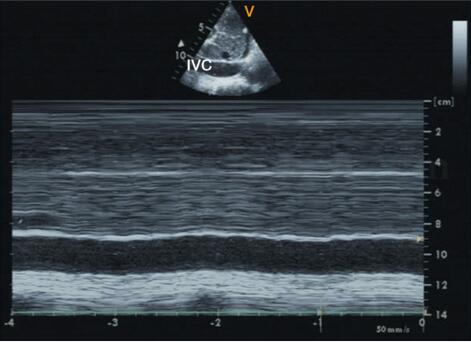

1﹒M型超声心动图 在M型超声心动图检查时心包增厚可表现为单条增厚的强回声线、两条同向移动的回声线或多条平行不动的回声线等,但上述表现特异性不强。缩窄性心包炎的其他征象包括主动脉波群和二尖瓣波群变化。可有双心房增大;左室后壁运动异常(舒张早期突然向后移动、舒张中晚期移动幅度明显减小或停止,使舒张期后壁内膜面呈斜直后移继以平直走行的直线样运动图形);室间隔舒张早期V字形凹陷(notch切迹);前室间隔运动异常(舒张早期突然向前运动,继之突然向后运动)、二尖瓣前叶EF斜率增快;下腔静脉增宽,塌陷指数减低,见图2‐1‐231。

图2‐1‐231 M型超声心动图显示下腔静脉扩张,塌陷指数减低